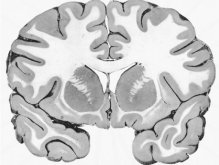

La materia gris corresponde a aquellas zonas del sistema nervioso central de color grisáceo integradas principalmente por somas neuronales y dendritas carentes de mielina. Se asocia con la función del procesamiento de información o del razonamiento. La cantidad de esta sustancia gris muchas veces se considera directamente proporcional a la inteligencia de un ser vivo.